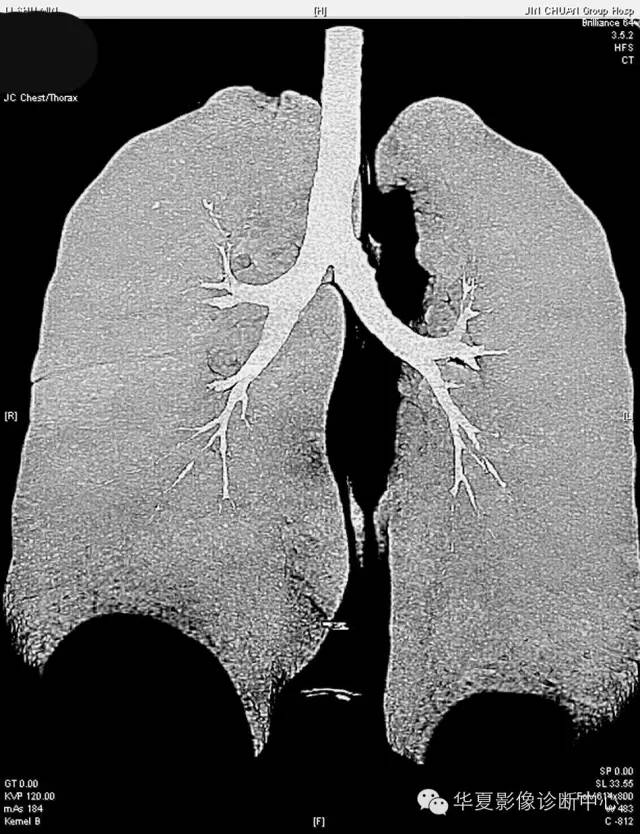

女,56岁,其父因肺癌去世,自觉胸部疼痛不适来诊要求拍胸片。

检查结论:

(右)肺中分化鳞状细胞癌。浸及胸膜。支气管残端切净。淋巴结未见癌转移(0/10)。